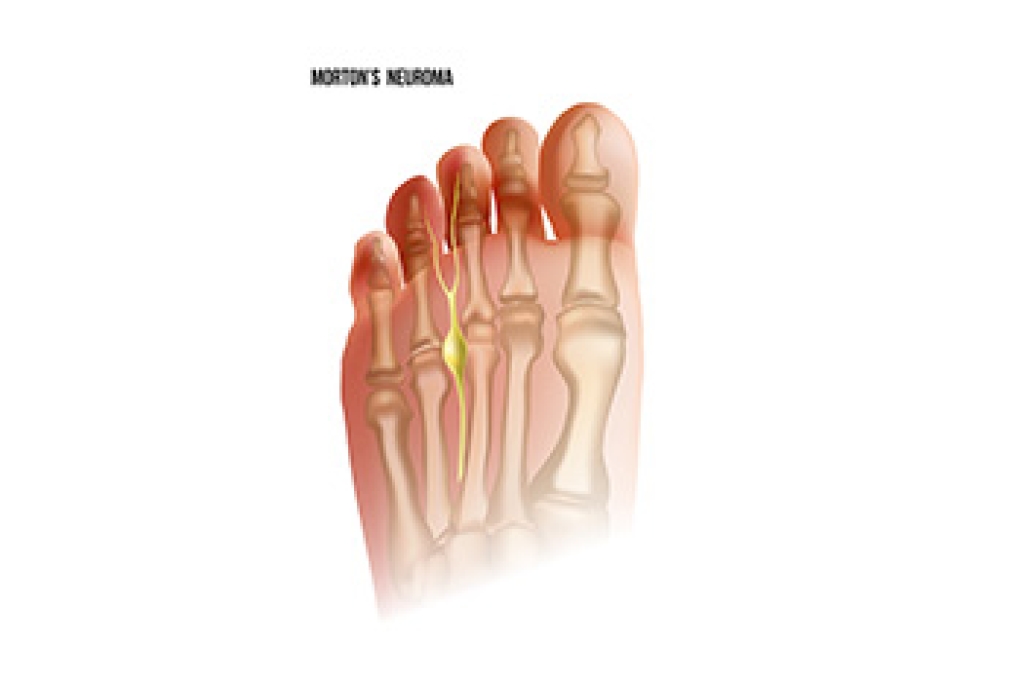

Podiatric Care For Morton’s Neuroma

Morton's neuroma is a condition that affects the forefoot. Despite its name, it is not a true neuroma but rather a result of nerve fibrosis. This fibrosis occurs due to pressure or repetitive irritation, resulting in the thickening of the digital nerve, typically found in the third or second intermetatarsal space. Managing Morton's neuroma involves various treatment options. Orthotics, which are custom-made shoe inserts, can provide relief by altering foot mechanics and reducing pressure on the affected nerve. Steroid injections can also be administered to alleviate inflammation and pain. In more severe cases, surgical excision may be necessary, typically performed through a dorsal approach. Successful management of Morton's neuroma relies on several critical factors. If you feel you have Morton’s neuroma, it is suggested that you schedule an appointment with a podiatrist. A thorough examination is essential to accurately diagnose and treat this condition.

Morton’s Neuroma

Morton's neuroma is a painful foot condition that commonly affects the areas between the second and third or third and fourth toe, although other areas of the foot are also susceptible. Morton’s neuroma is caused by an inflamed nerve in the foot that is being squeezed and aggravated by surrounding bones.

What Increases the Chances of Having Morton’s Neuroma?

- Ill-fitting high heels or shoes that add pressure to the toe or foot

- Jogging, running or any sport that involves constant impact to the foot

- Flat feet, bunions, and any other foot deformities

Morton’s neuroma is a very treatable condition. Orthotics and shoe inserts can often be used to alleviate the pain on the forefront of the feet. In more severe cases, corticosteroids can also be prescribed. In order to figure out the best treatment for your neuroma, it’s recommended to seek the care of a podiatrist who can diagnose your condition and provide different treatment options.